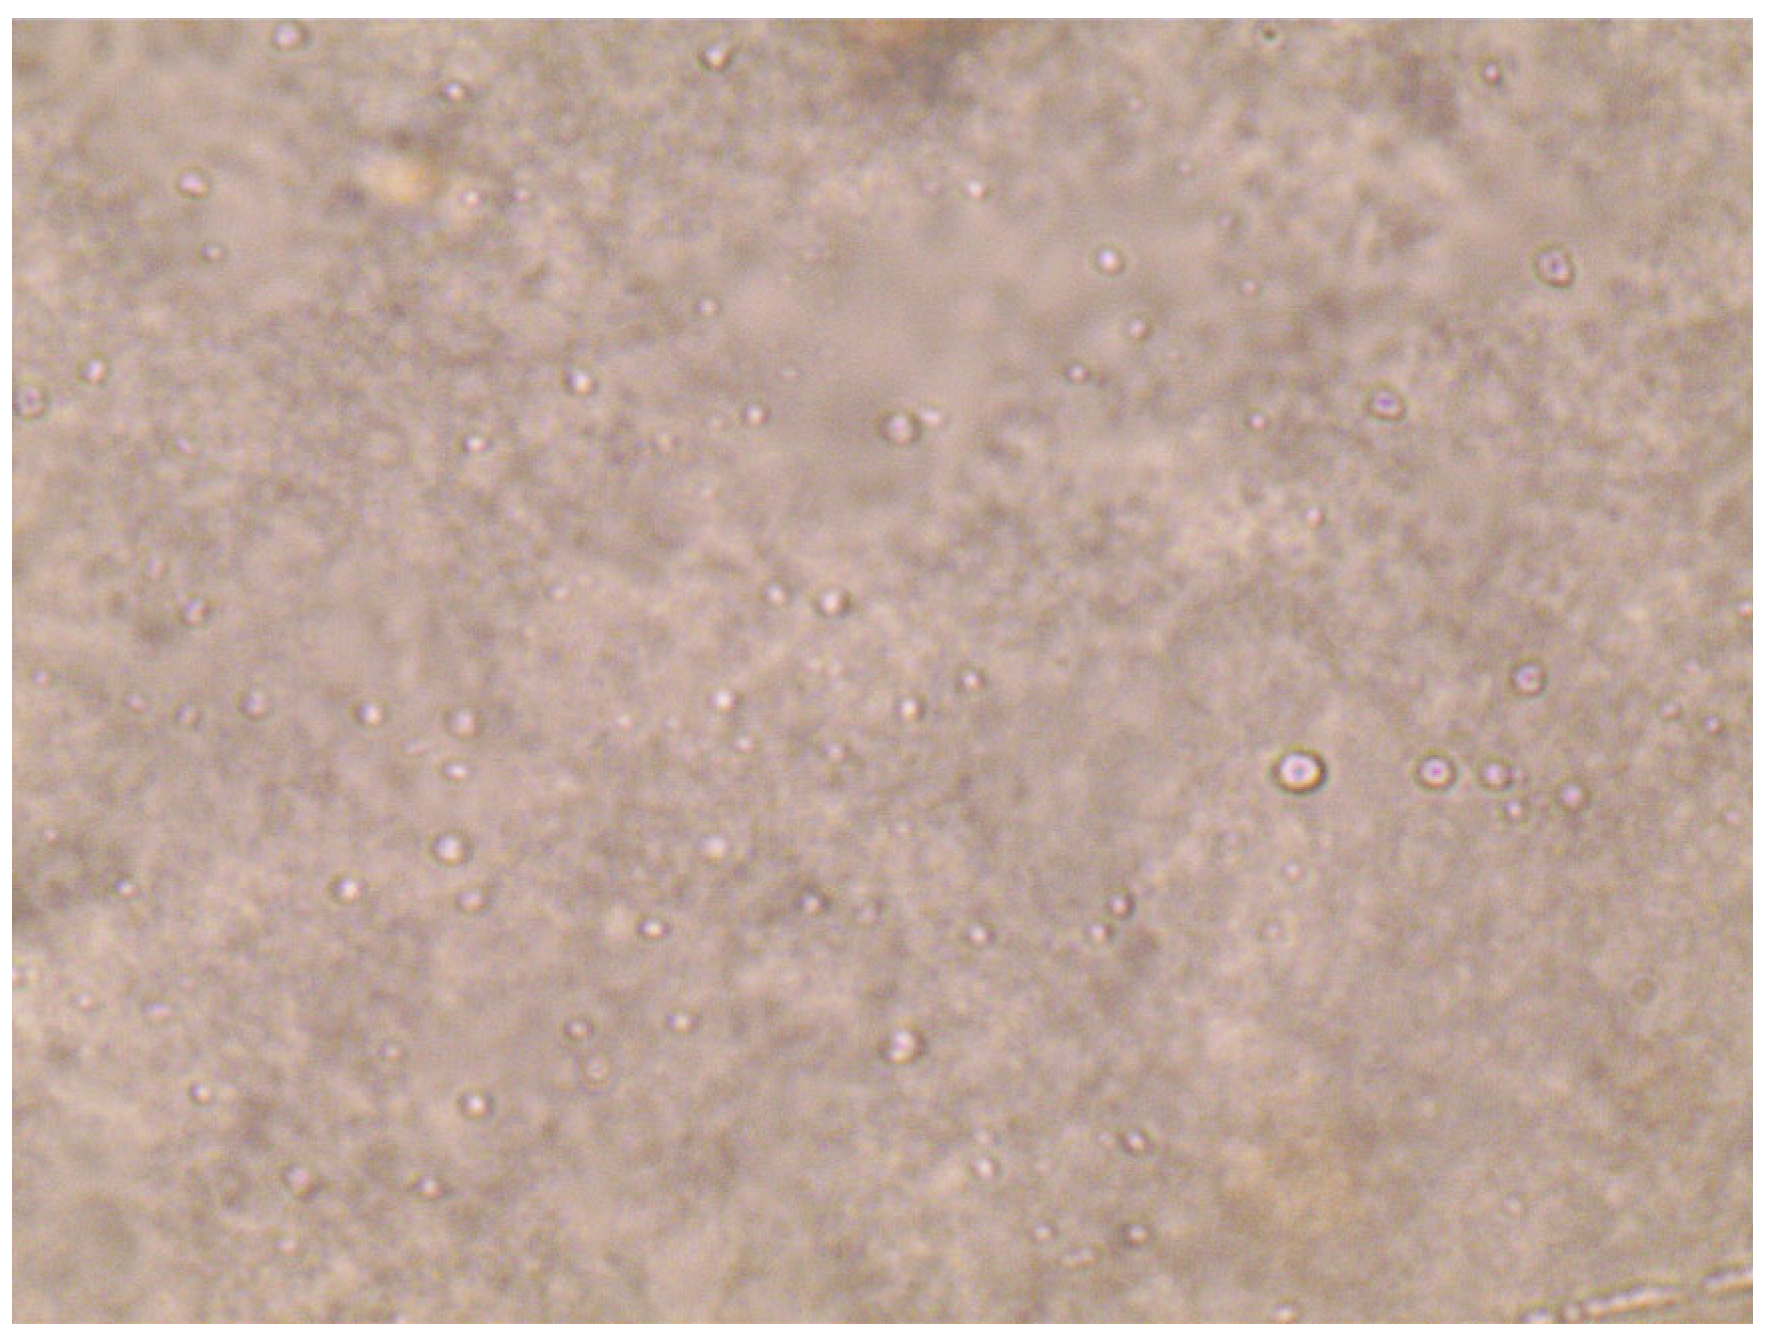

2.8. TEM

4.12.5. Morphology